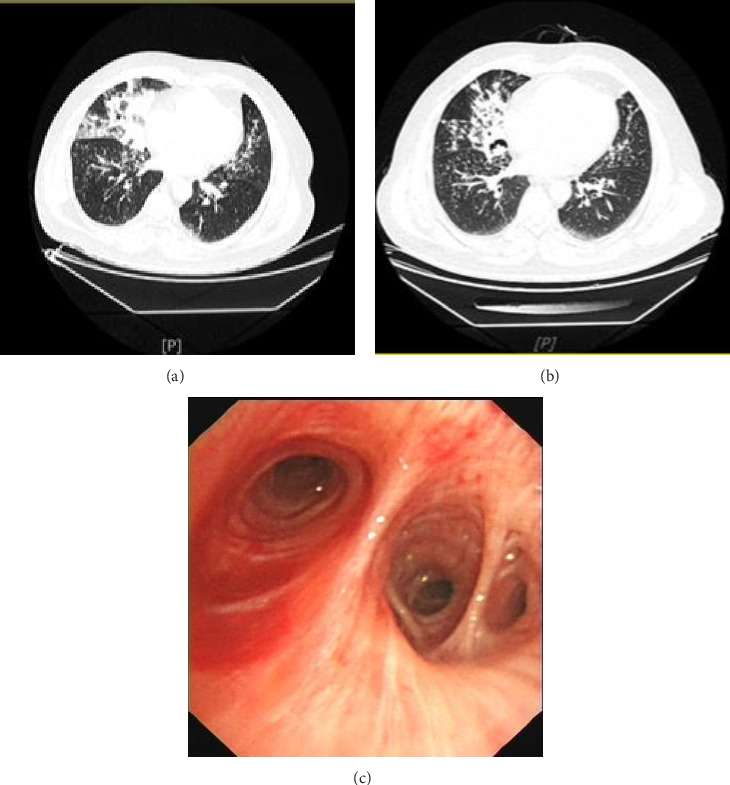

Exogenous lipoid pneumonia (ELP) is a rare disease with both acute and chronic forms. This paper primarily summarizes the diagnosis and treatment process of bronchoalveolar lavage combined with glucocorticoids treatment of acute ELP caused by aspiration of liquid hydrocarbons (e.g., kerosene and diesel fuel) at our hospital. Furthermore, the present study analyzes the advantages of bronchoalveolar lavage combined with glucocorticoids treatment of acute ELP.